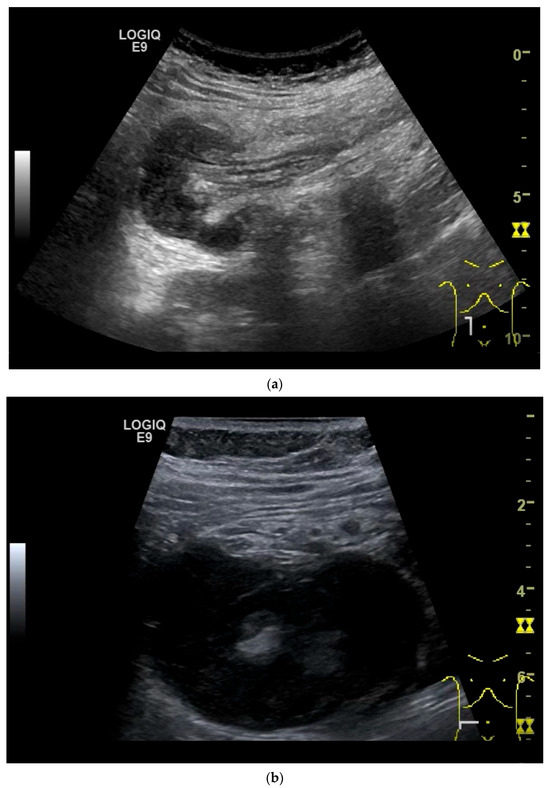

Figure 10.

Diffuse large B-cell lymphoma (DLBCL). In the right mid-lower abdomen, a large, smoothly circumscribed mass is present around the ileum (“pseudo kidney sign” (a)). Using a high-resolution linear transducer, the mass appears smoothly circumscribed and almost anechoic (b). The ileum runs centrally, and the echogenic wall is clearly defined (c). This wall does not merge into the mass. Since the mass is almost anechoic, it is also difficult in different transducer positions to distinguish whether it is a liquid lesion or a solid mass (b,c). CEUS with 2.4 mL SonoVue (9 MHz linear transducer) shows homogeneous arterial enhancement (d), but the intensity decreases with time in the venous phase (e). The ileal wall enhancement centrally within the mass is more intense than that of the tumor (d,e).